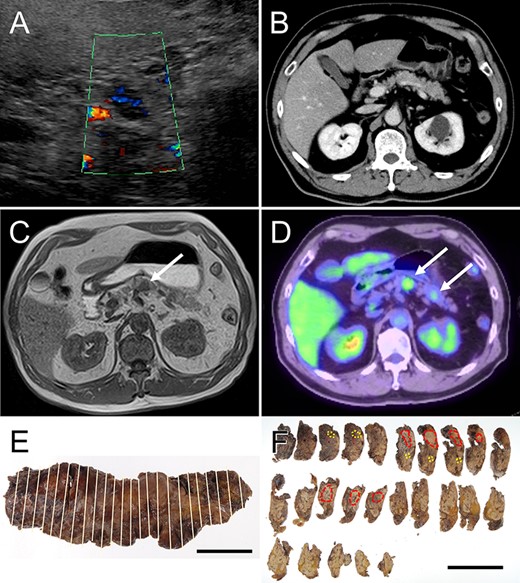

Radiological features and macroscopic findings of Case 1. (A) Abdominal ultrasonography: hypoechoic mass was demonstrated in the pancreas. (B) CT: no mass lesion was detected. (C) MRI: T1-weighted image showed nodular mass of low intensity (white arrow). (D) FDG-PET: two nodular masses with high SUV were detected in the pancreas (white arrows). (E) The macroscopic appearance of the resected pancreas. (F) Two nodular lesions (red circles) and foci of small lesions (yellow circles) were determined by histological examination on the cut surface.

A nodular mass was noted in the body or tail of the pancreas by USG in three cases (Figs 1–3). Endoscopic ultrasound-guided fine needle aspiration gave negative result in all patients. No lesion was detected by computed tomography (CT) (Fig. 1B and Table 1). Low-intensity mass was detected in the body or tail with T1-weighted imaging of magnetic resonance imaging (MRI: Fig. 1C and Table 1). 18F-fluorodeoxyglucose positron-emission tomography (FDG-PET) detected two lesions with high standardized uptake value (SUV) in the body and tail in Cases 1 and 2 (Figs 1D and2A and Table 1) and one lesion in the body in Case 3 (Fig. 3A and Table 1). In the resected pancreas, two lesions were found in the body and tail of the pancreas in Cases 1 and 2 (Figs 1F and2C, red circles) and one lesion of the pancreatic body in Case 3 (Fig. 3C, red circles). Small foci of lymphoid hyperplasia were noted in all cases (Figs 1F, 2C and3C, yellow circles).